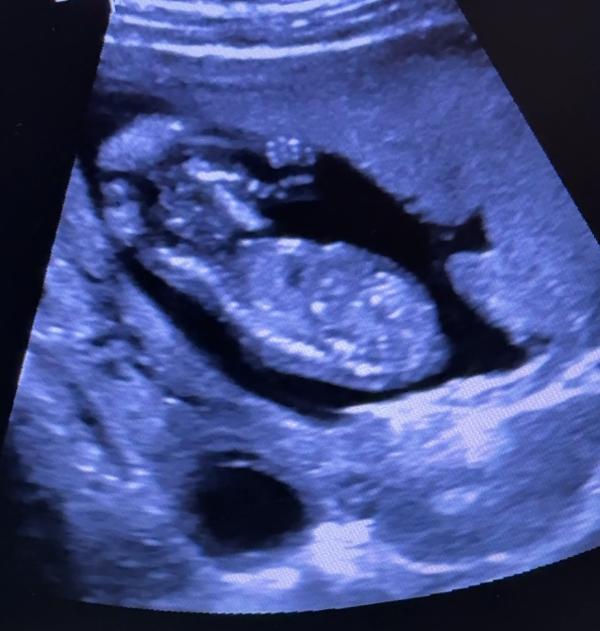

Повидались с доченькой. Ручкой помахала, спинку повыгибала, уже трогает мои стеночки. Жаль пока не ощущается. Хотя иногда есть такое чувство😇